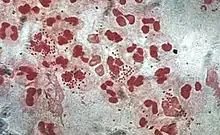

Monocytes develop in the bone marrow and reach maturity in the blood. Mature monocytes have large, smooth, lobed nuclei and abundant cytoplasm that contains granules. Monocytes ingest foreign or dangerous substances and present antigens to other cells of the immune system. Monocytes form two groups: a circulating group and a marginal group that remain in other tissues (approximately 70% are in the marginal group). Most monocytes leave the blood stream after 20–40 hours to travel to tissues and organs and in doing so transform into macrophages[70] or dendritic cells depending on the signals they receive.[71] There are about 500 million monocytes in one litre of human blood.[5]